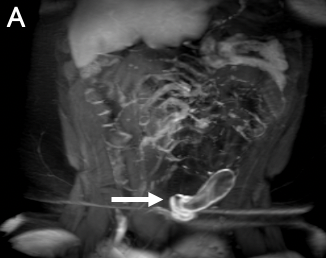

A pelvic ultrasonography scan showed a dilated, blind-ended, fluid-filled tubular structure in the right lower abdomen, which raised suspicion for appendicitis (Figure 1). A pediatric surgeon was consulted, and a computed tomography scan was performed, results of which showed a heterogenous complex lesion within the lower abdominal mesentery. Magnetic resonance imaging (MRI) of the abdomen and pelvis revealed a hydrosalpinx with thick peripheral enhancement, raising suspicion for superimposed infection and inflammation, as well as an arcuate uterus (Figure 2).

Figure 2. Coronal (A) and axial (B) T1 postcontrast, fat-saturated, maximum-intensity-projection MRI scans were performed of the abdomen and pelvia within 24 hours of the ultrasonography scans in Figure 1. Results demonstrated a thick-walled, blind-ending, tubular structure in the left lower quadrant that was anterosuperior to the uterus (asterisk). These scans confirmed a dilated, tortuous, fluid-filled fallopian tube (arrows).